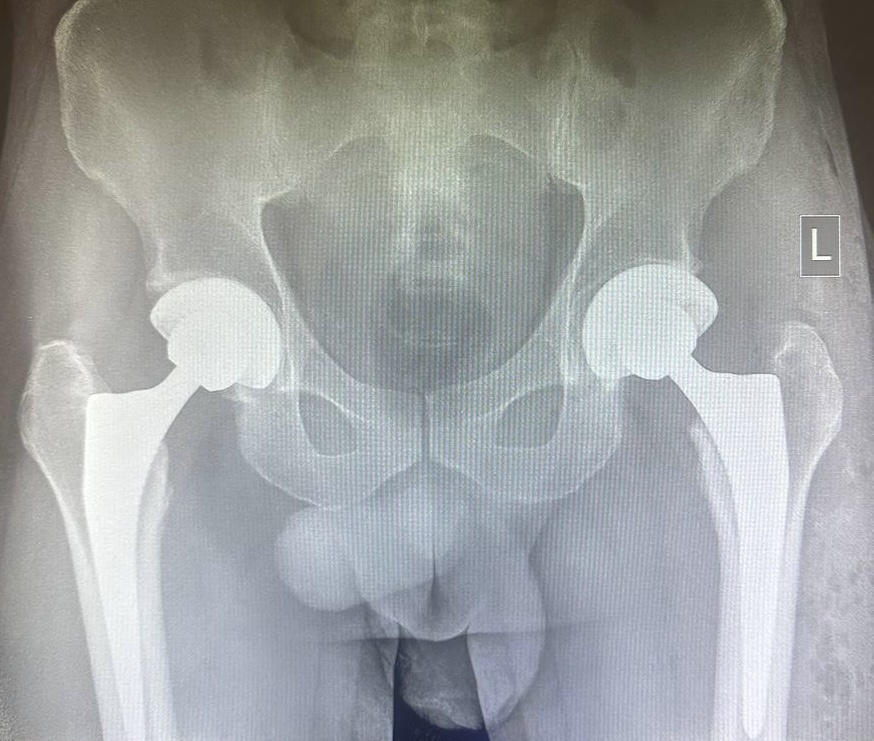

Одномоментное эндопротезирование тазобедренных суставов. Прямой передний доступ.

Двусторонний коксартроз встречается примерно у 20% пациентов, обращающихся по поводу боли в тазобедренном суставе, а двусторонний асептический некроз за последнее время привел к уменьшению среднего возраста у оперируемых пациентов на нексколько лет.

До 22% пациентов после первичного THA впоследствии нуждаются в контралатеральном эндопротезировании.

Так стоит ли делать поэтапные операции или же лучше выполнить все одномоментно с использование доступа DAA (ERAS protocol)?